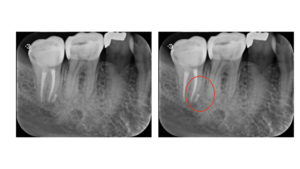

違和感を訴え来院した患者さんです。違和感のある右下一番奥の歯は神経を抜いた根管治療がすでに行われた状態です。

手前の根っこである近心根の側面に根尖病変がみられ大きく骨がなくなっている状態が確認できます。

根尖病変が大きく、抜歯をする可能性もありますが、古い被せ物を外し、根管治療を行いました。(手前の歯も虫歯の治療を行っています)

2年後にレントゲンを撮影すると、炎症により骨がなくなっていた部分がなくなっています。

根管治療により歯の中の虫歯菌を取り除くと、なくなった骨が元に戻ってくれるのです。